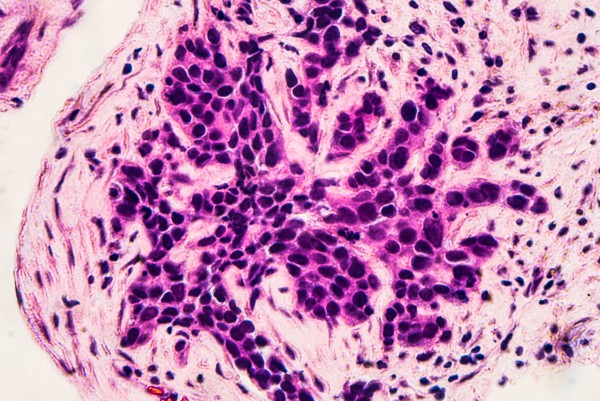

Ацинарная аденокарцинома — это один из типов злокачественных опухолей простаты, который делится на два подтипа: мелкоацинарную и крупноацинарную. Мелкоацинарная форма характеризуется небольшими размерами и включает мелкие, близко расположенные структуры паренхимы. Крупноацинарная опухоль, напротив, имеет больший размер и состоит из крупных железистых элементов.

Ацинарная аденокарцинома предстательной железы. Карцинома простаты – это рак предстательной железы, развитие которого начинается из эпителия альвеолярно-клеточных элементов железы.

Будучи наиболее частым злокачественным гистологическим подтипом рака предстательной железы, ацинарная аденокарцинома предстательной железы (ПАА) имеет ряд доброкачественных имитаторов, включая простатические или непростатические поражения, а также нормальные структуры, что может привести к ошибочной диагностике и неправильному лечению.

Что такое аденокарцинома ацинарного строения?